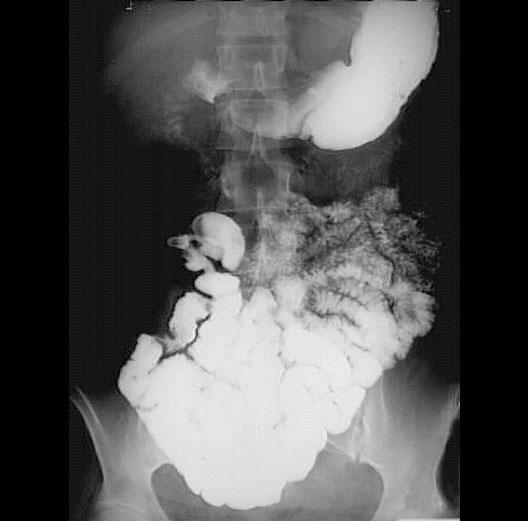

Small Bowel Follow Thru

1. Stomach

2. 1st part of duodenum

3. 2nd part of duodenum

4. Jejunum

5. Ileum